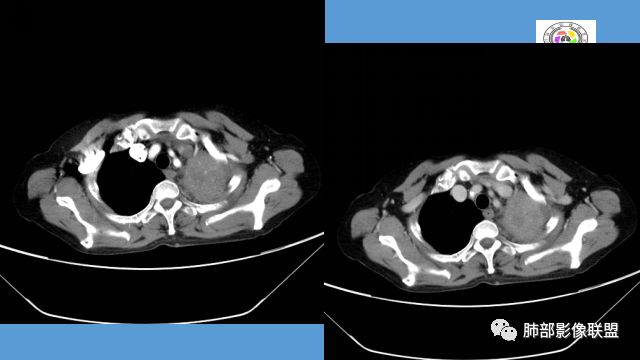

中年女性,反复咳嗽咳痰4月,加重半月,咳嗽,咳黄痰。胸CT:左肺体积缩小,左肺上叶病变,病灶内可见支气管征,病灶边缘可见棘突样改变,病灶周围可见结节状卫星灶,纵隔可见淋巴结肿大,部分淋巴结可见钙化灶。增强CT病灶内可见低密度坏死区,冠状位病灶内支气管可见扩张,病灶整体呈收缩,考虑患者为良性慢性感染性病变,结核?放线?,建议支气管镜检查。

考虑结核伴混合感染。中青年女性,持续低热、不正规抗感染症状加重。左上肺低密度肿块,左上固有段支气管未显影(结核侵蚀干酪样坏死),左上舌段支气管通畅但增厚变形。左下肺树芽征新发支气管播散。鉴别:粘液腺癌

中年女性,反复咳嗽咳痰4月。胸CT:左肺上叶块状病变,病灶内可见支气管征,边缘见棘突样改变,周围可见结节状卫星灶,纵隔可见淋巴结肿大,部分淋巴结可见钙化灶。增强CT病灶内可见低密度坏死区。病灶整体呈收缩,考虑为良性病变,结核可能性大,建议支气管镜检查。

左肺上叶软组织肿块,密度不均匀,边界清晰,不均匀强化伴坏死,支气管走行僵直

晨读:左肺上叶实变,边缘不整,部分膨隆,其内支气管有狭窄有扩张,周围小叶间隔增厚,左肺下叶背段可见气腔结节,树芽征,边缘模糊,肺门及纵膈淋巴结钙化,考虑结核。鉴别肺炎型肺癌。

左上胸缩小,但是左上叶部分实变,边缘膨隆,内部有含气支气管,粘液栓,近端支气管堵塞

上叶支气管堵塞处稍萎缩、凹陷,附近壁增厚,内可见小点状钙化